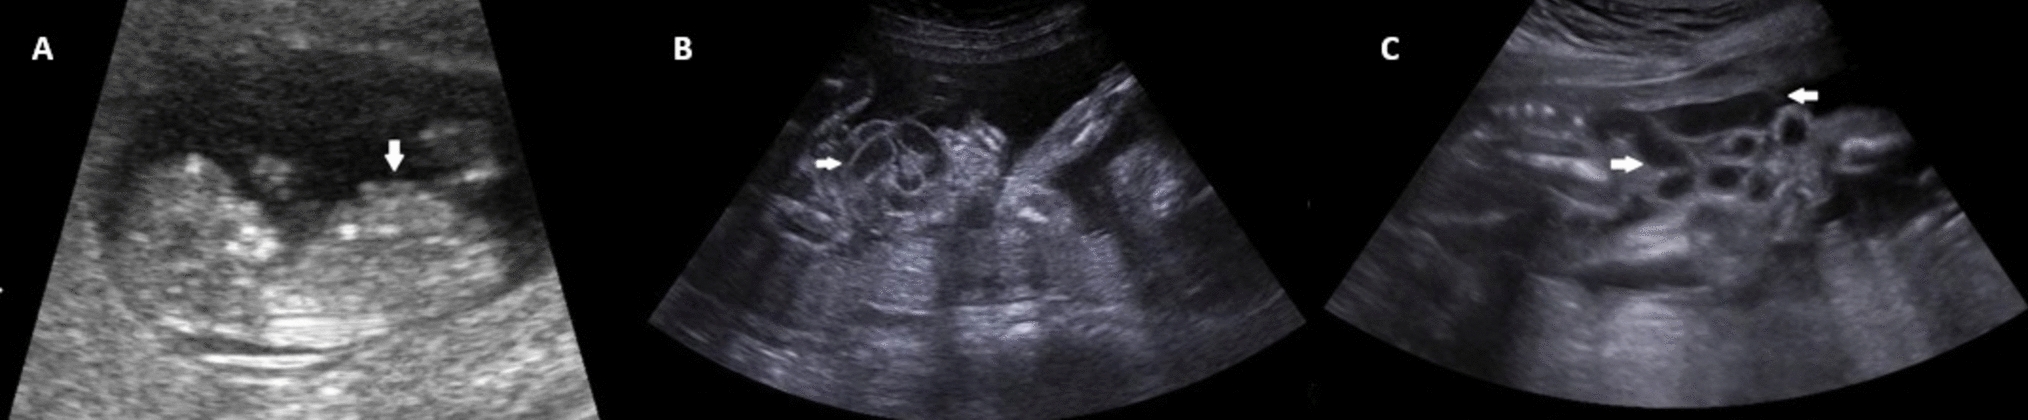

This was a retrospective observational cohort study of 154 patients with endometriosis who underwent laparoscopic or robotic endometriosis excision between April 2021 and September 2022 by a single surgeon in a multidisciplinary endometriosis centre. Clinical criteria such as age, demographics, menstrual history, previous endometriosis surgeries, size and location of endometriomas, along with clinical symptoms such as dysmenorrhea, dyschezia, infertility, dyspareunia, urinary frequency and rectal pain were documented. The #ENZIAN [2021] classification was used to assess the distribution of disease.

Mean age of the patients was 32.25 ± 6.107 years, and mean BMI was 23.9 ± 3.36 kg/m2. 47.2% had taken medical treatment for a period of 5.9 ± 11.7 months. Regarding parity, 75.4% were nulliparous, and 40.8% patients had infertility as co-existing complaint. According to #ENZIAN, the left ovarian involvement was observed in 67.4% and bilateral involvement noted in 46.1%. A (rectovaginal vagina and septum) was involved in 61% cases, B (uterosacral ligaments and pelvic wall) 63.58% on left and 60.33% on right and C (rectum and sigmoid colon) 33.1% cases.